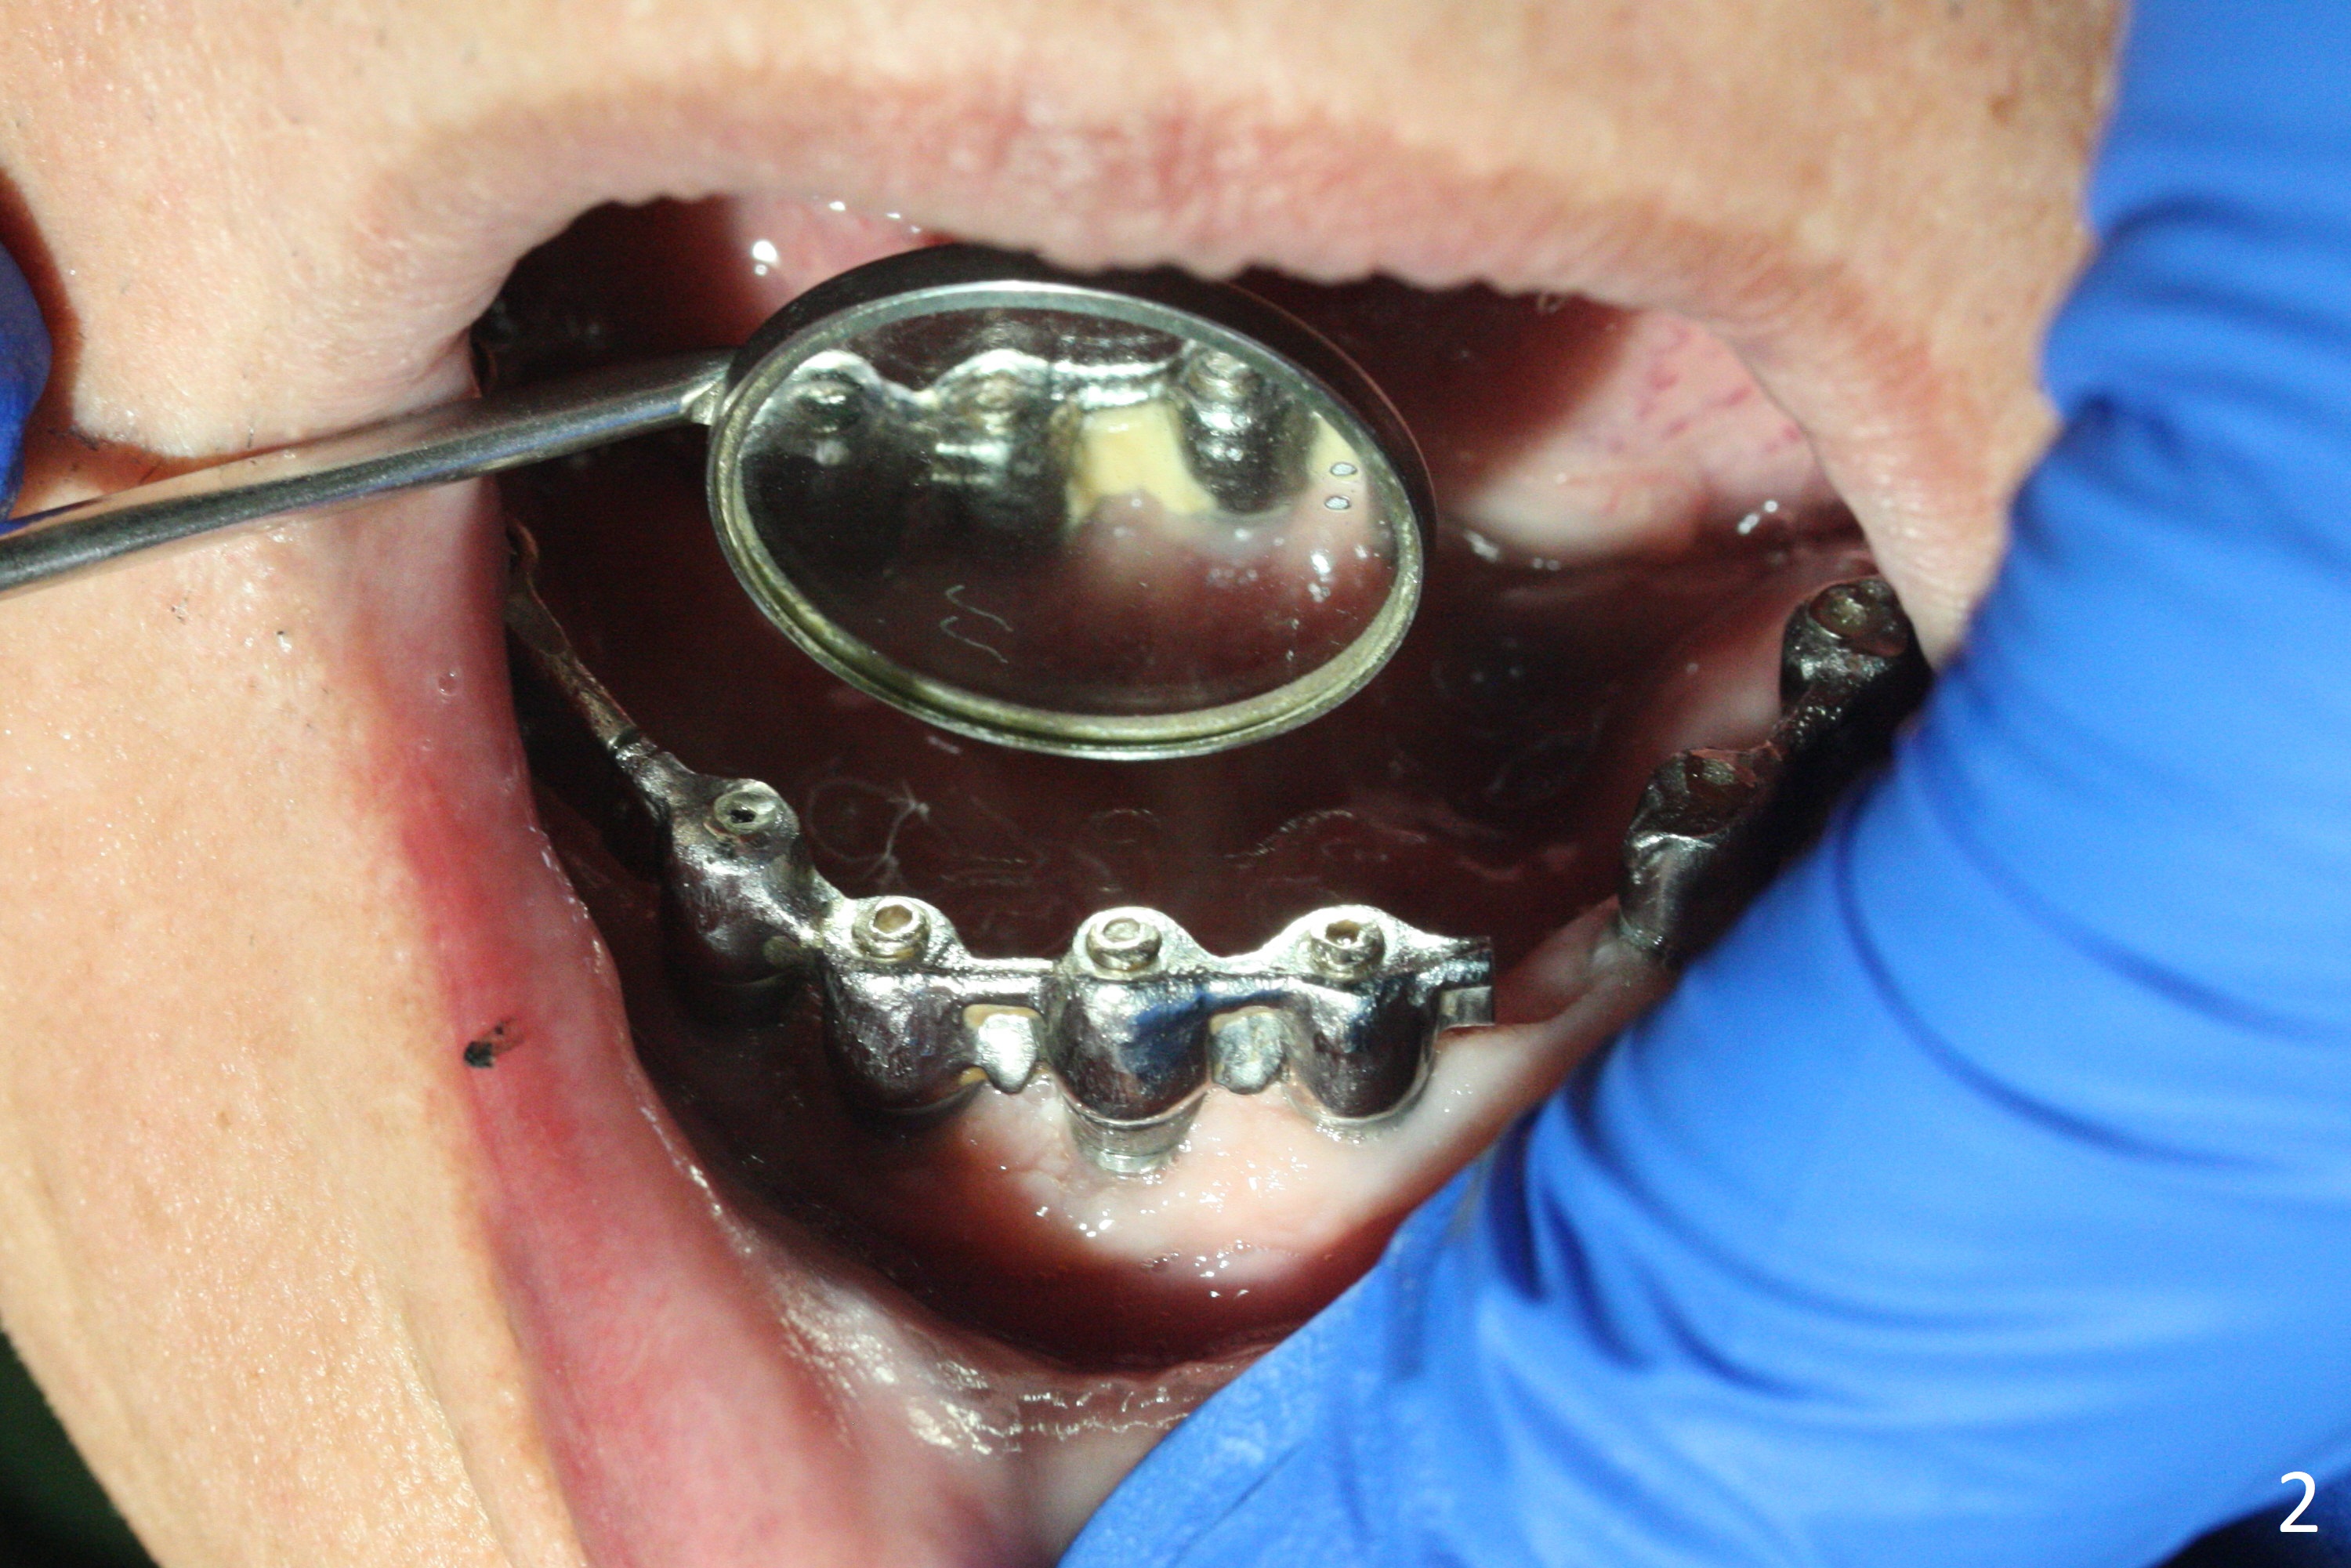

A 77-year-old man presents to clinic with chief complaint of loose lower denture, which is ~ 15 years old (Fig.1-6). The implants were placed ~ 30 years ago. There is wear and crack of the denture teeth (Fig.3). When the denture is remade, make metal occlusal surface at the premolar and molar region. An extra existing denture will be sent to lab for reference. What is the best method to take the lower impression? Block metal framework undercuts? Alginate or PVS?